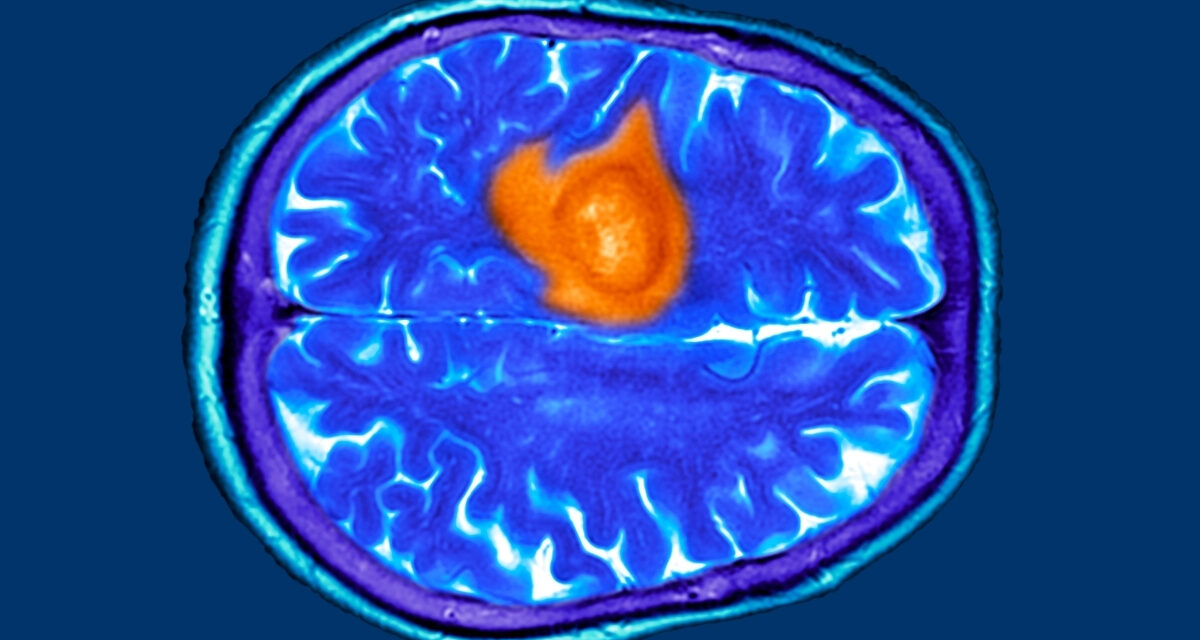

The 7 Warning Signs of Brain Cancer You Might Easily Miss